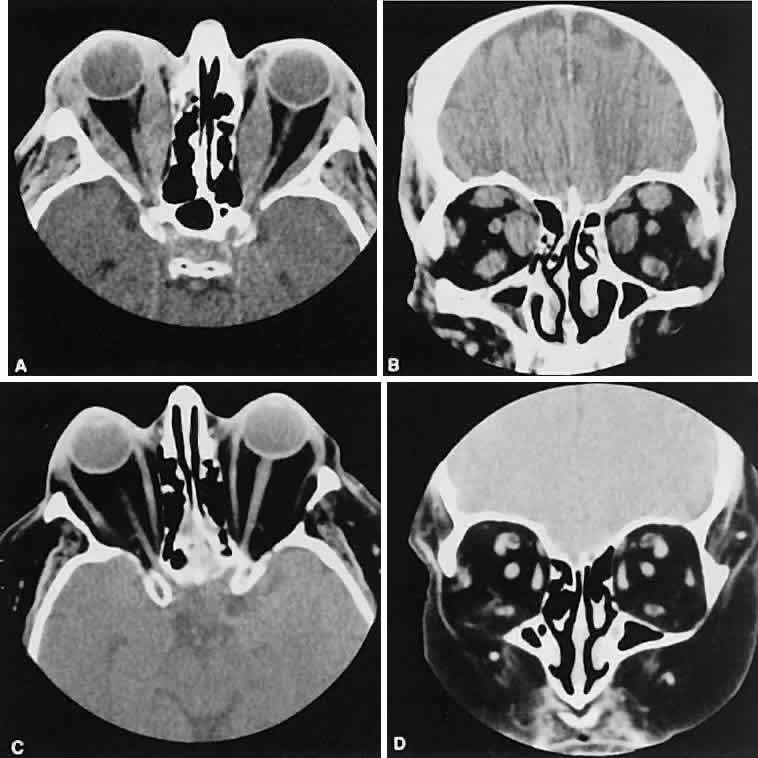

Metastatic disease accounts for 2% to 10% of all orbital tumors.69,70 As a generalization, childhood metastases are from undifferentiated sarcomas, whereas adult metastases are from postembryonal carcinomas.

Radiographic evaluation can show either infiltrative or circumscribed masses. Some tumors display a predilection for metastasizing to certain structures, such as prostate carcinoma to bone and cutaneous melanoma to EOMs (Fig. 21). Evidence of bilateral disease at presentation ranges from 7% to 9%, with the prime example being neuroblastoma.71

Fig. 21. A. Axial view shows bilateral involvement from metastatic breast carcinoma. An amorphous infiltrative soft-tissue mass is more apparent in the right orbit, which encases the globe, producing clinical and radiographic enophthalmos. Cutaneous melanoma metastatic to the superior rectus muscle is depicted on axial (B) and coronal (C) views. A locally enhancing and asymmetric enlargement is restricted to the right superior rectus muscle. These features distinguish this lesion from Graves' orbitopathy.